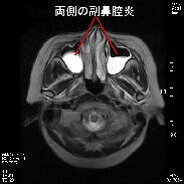

また緑内障など眼科的な問題で慢性的な頭痛を引き起こしている場合もありますし,耳鼻科的疾患である副鼻腔炎(蓄膿症)が原因となっている場合も結構見られます.最近はアレルギー性鼻炎の方が多く2次的に急性副鼻腔炎を引き起こしている方も多く見られます.左の写真は副鼻腔炎の症例ですが,正常例と比較すると膿の貯留により副鼻腔が白くなっています.これらの頭痛も検査をすればすぐに原因が判明します.このように頭痛の原因は思いもよらないところにある場合があり,慢性的な頭痛にお悩みの方は一度検査をお勧めします.